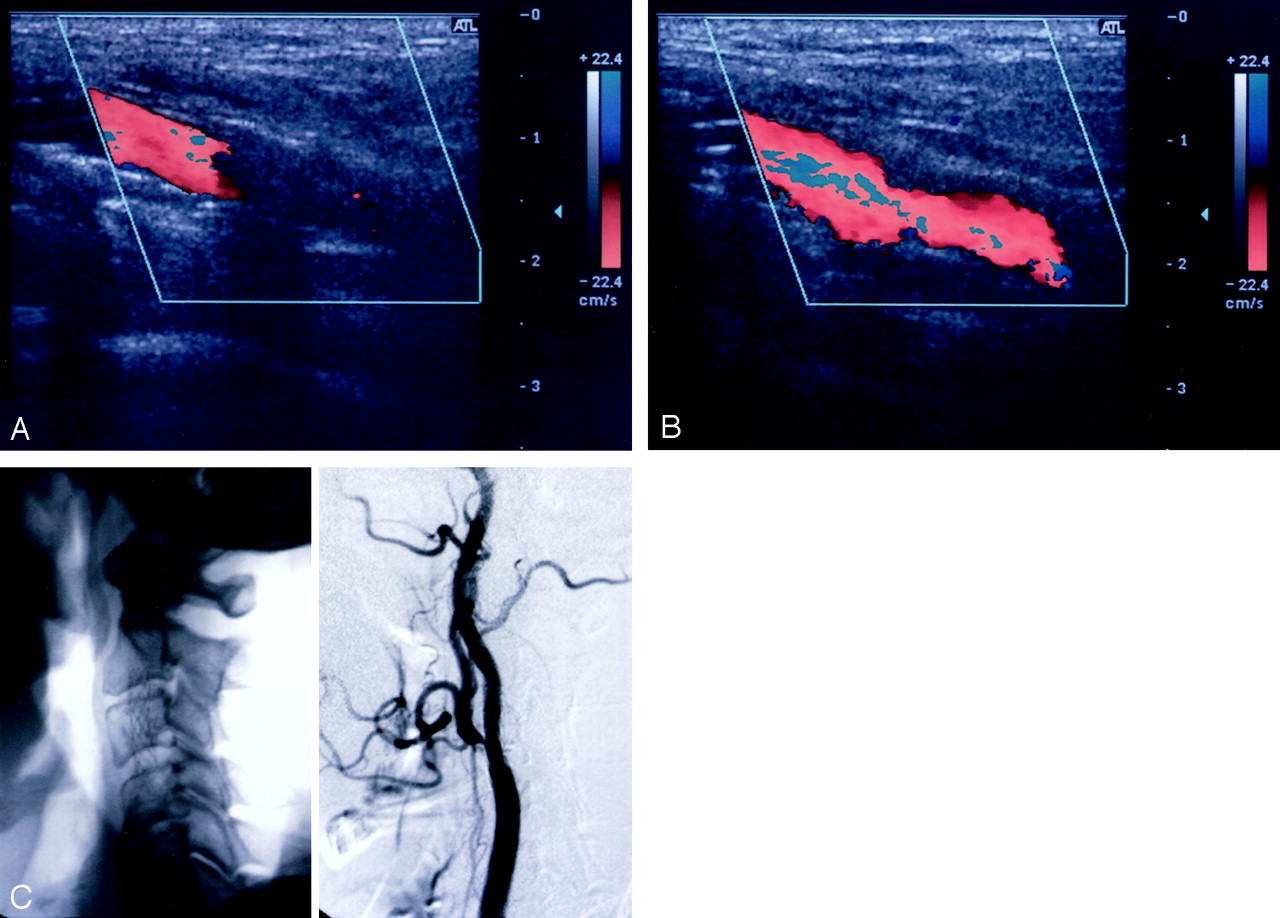

In the two patients who underwent overlapped stent placement, none of the original CCCD images completely showed flow in the stents. After the administration of the contrast agent, continuous visualization of the color-coded bloodstream, even in the overlapping part of the stents, was possible. These CE-CCCD images provided anatomic information almost equivalent to that possible with angiography (Fig 1).

Benefit of CE-CCCD sonography in a patient with overlapped stents (patient 14).

A, Nonenhanced CCCD image did not allow visualization of blood flow in the overlapped stents.

B, CE-CCCD sonogram provides anatomic information almost equivalent to that on the DSA image.

C, Corresponding lateral radiograph (left) and DSA (right) images.